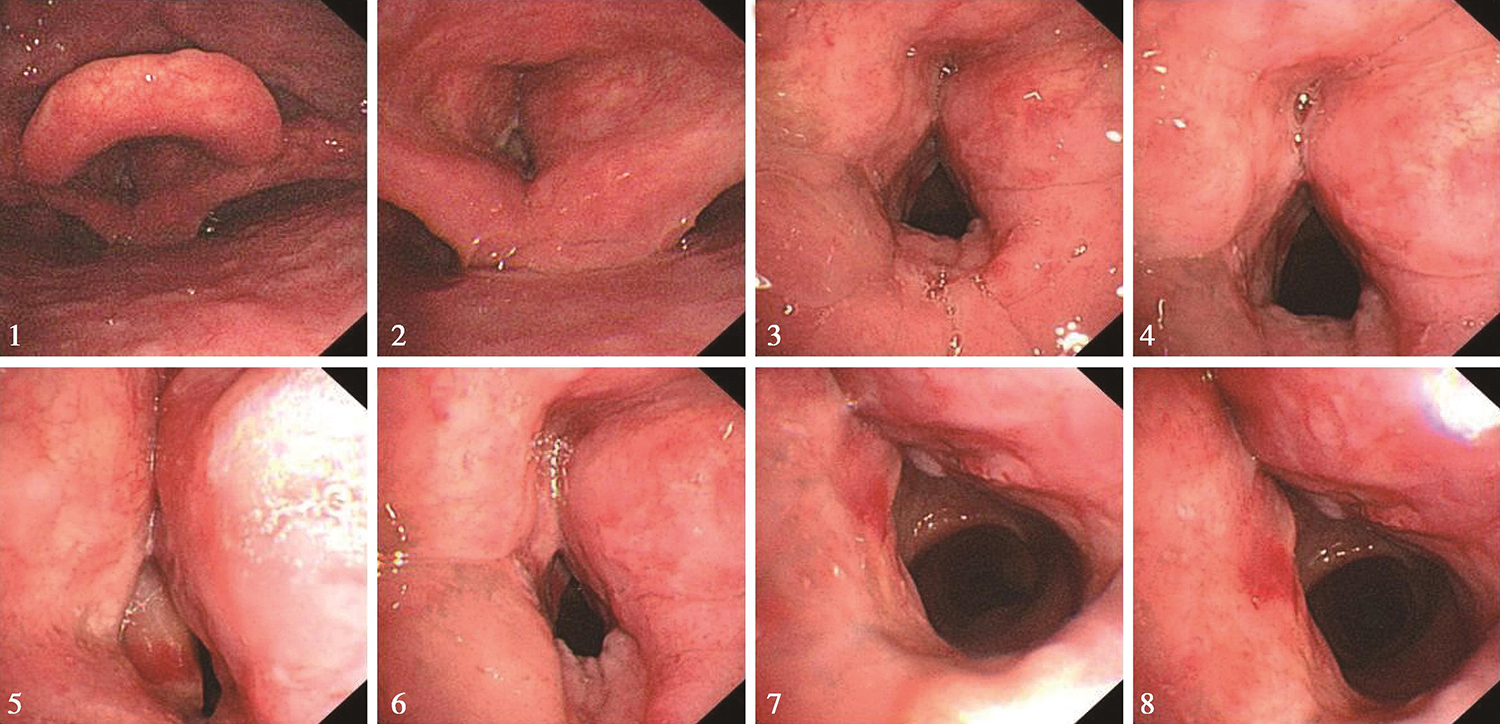

1.2017年3月17日电子鼻咽喉镜检查

内镜所见:鼻腔进镜顺利。鼻咽部结构完整,黏膜光滑,未见明显异常。口咽双侧扁桃体未见肿大。舌根部淋巴滤泡增生。下咽部表面基本平整,未见明显异常。喉部会厌及左侧劈裂结构基本正常,右侧室带明显增厚,右侧劈裂略显肿胀,病变向下侵及右侧声带,未侵及声门下(图1)。左侧声带前端被遮盖,情况不明。左右半喉活动尚可。

图1右侧声门上新生物

内镜诊断:喉癌。